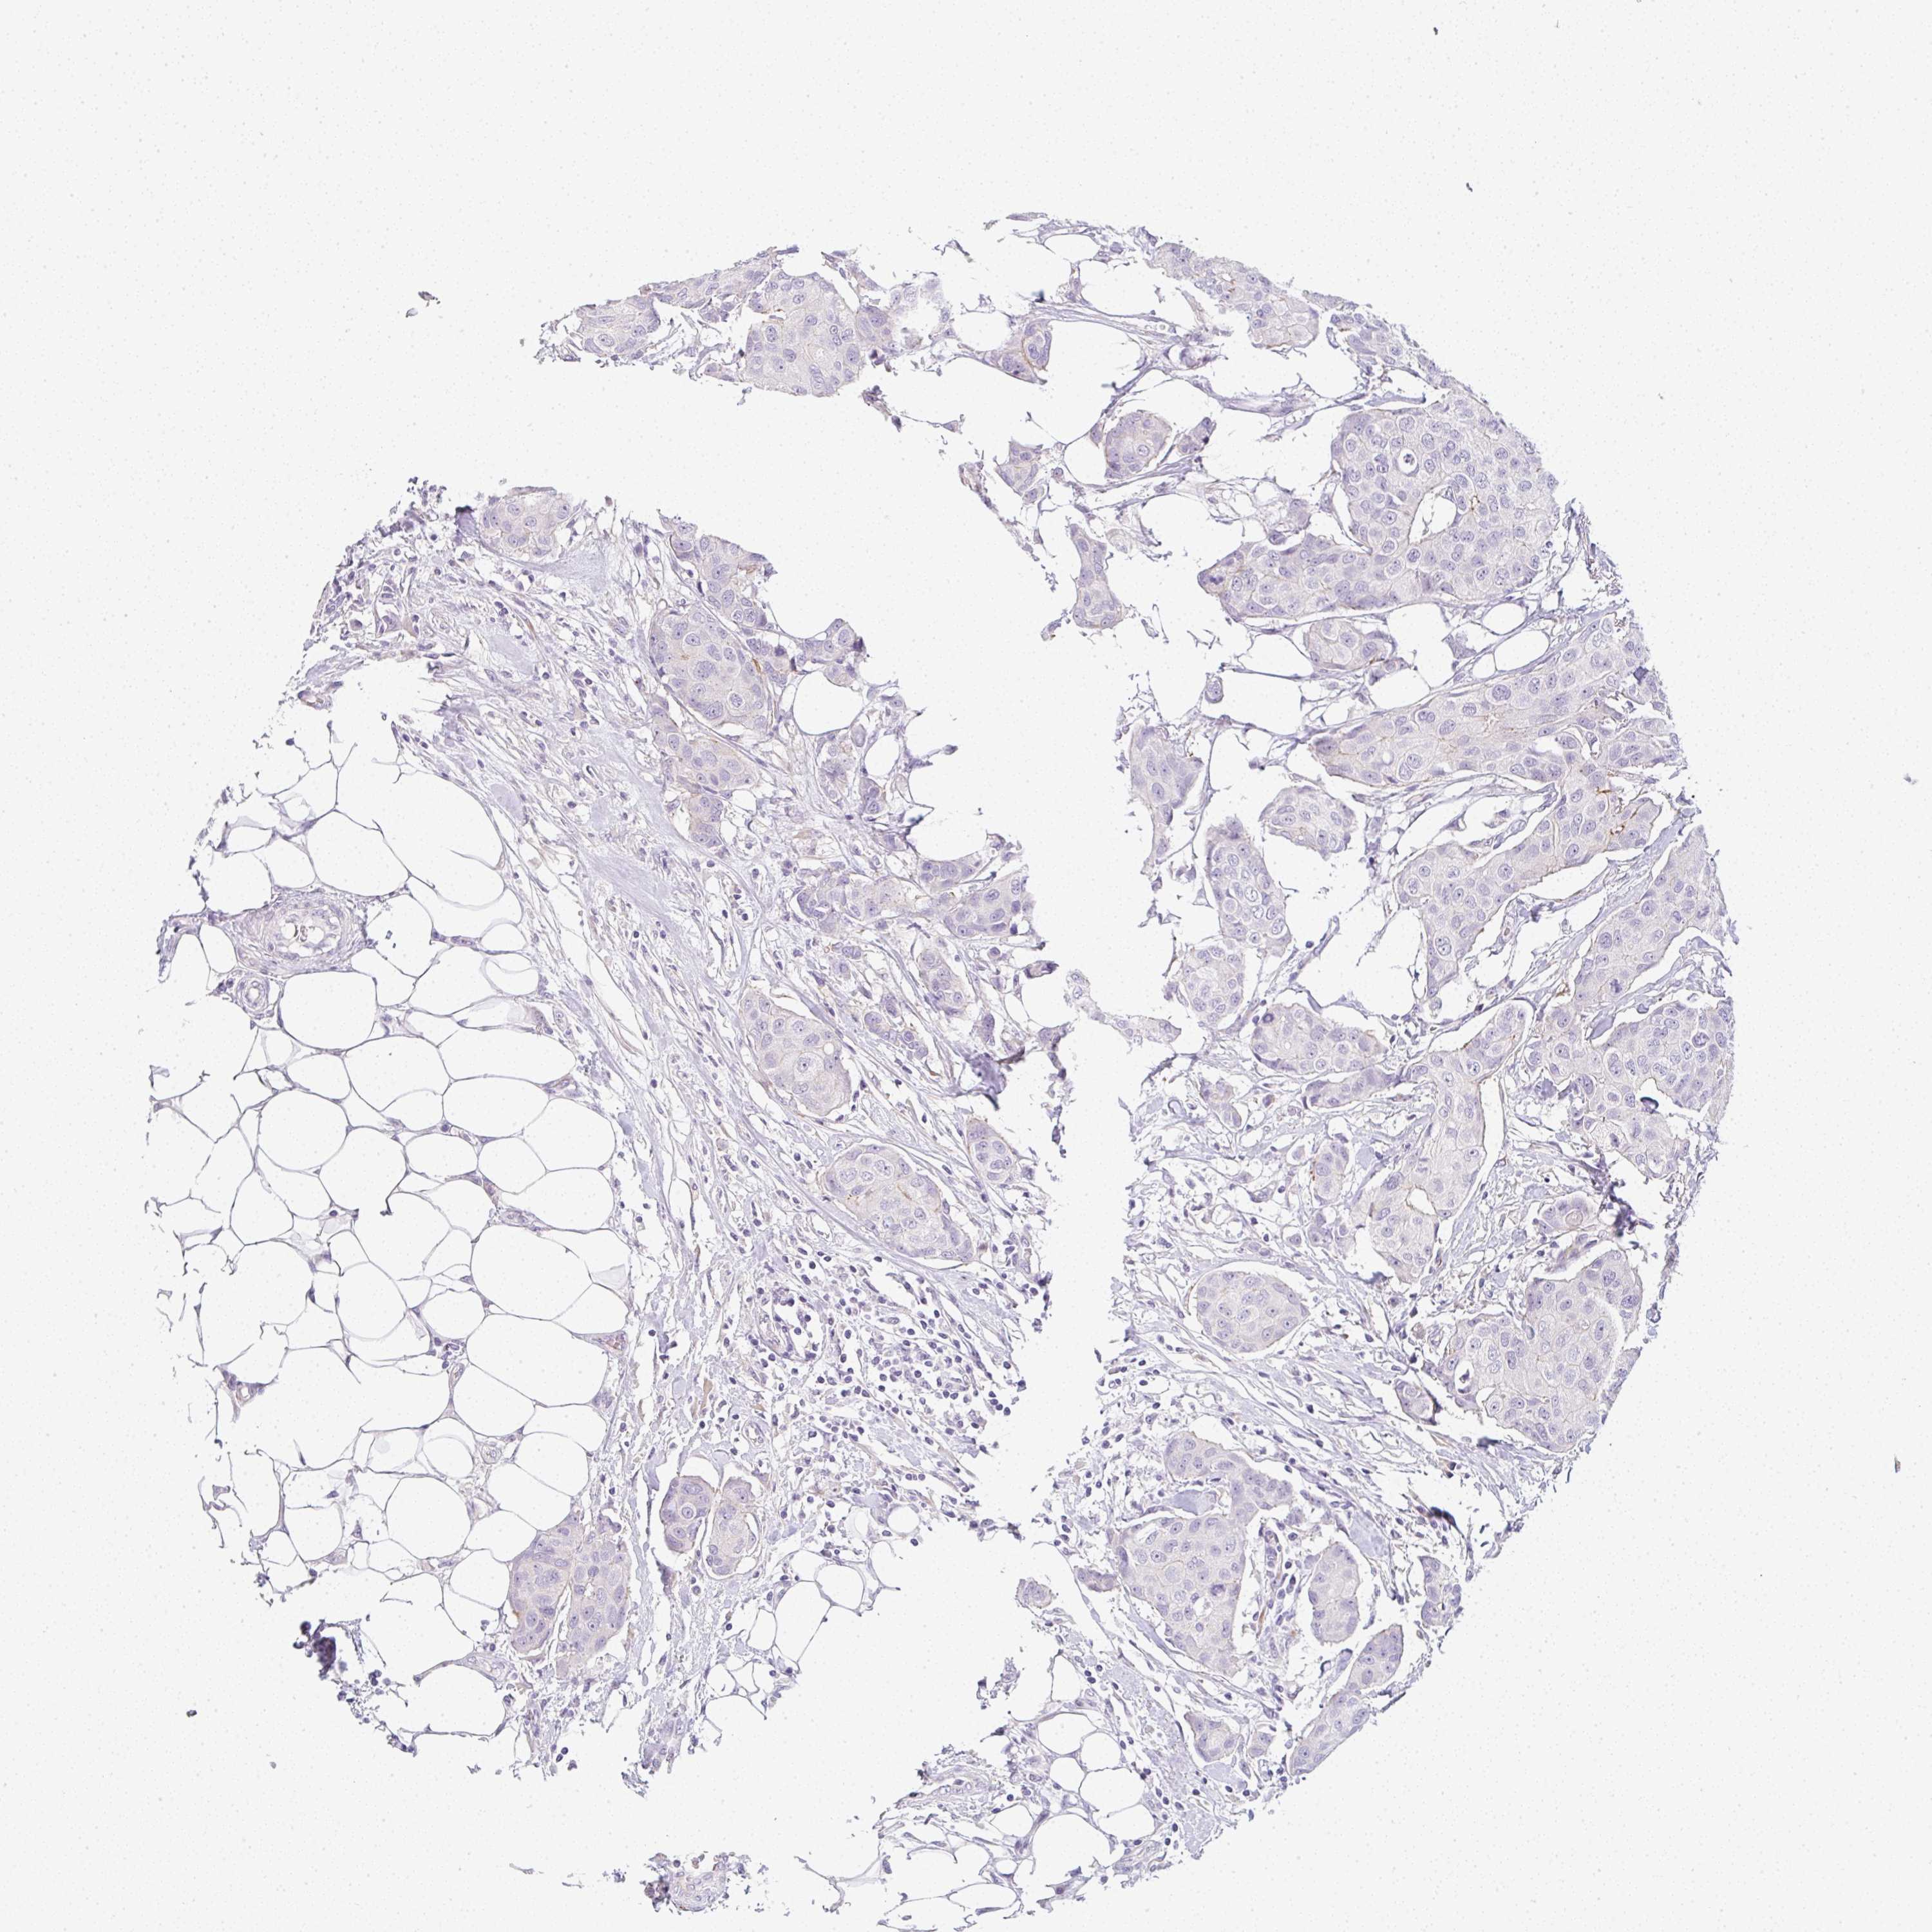

BRCA TCGA BRCA VALIDATION PROTEIN EXPRESSION

ANTIBODIES

AND

VALIDATION